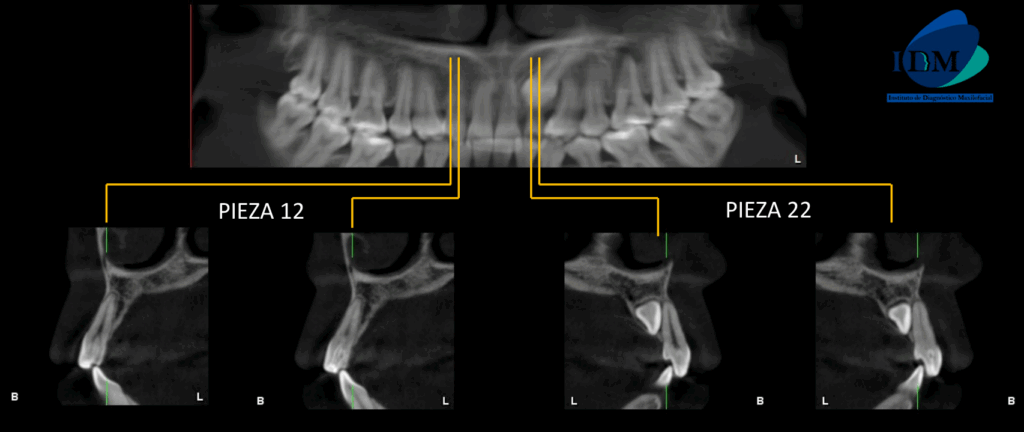

A la evaluación de la tomografía de campo mediano en cortes axiales, transaxiales y tangenciales se evidencia un detalle que en la panorámica paso un poco inadvertida y es que las piezas 12 y 22 presentan una alteración de la morfología coronaria compatible con dientes invaginados.

CORTES TRANSAXIALES